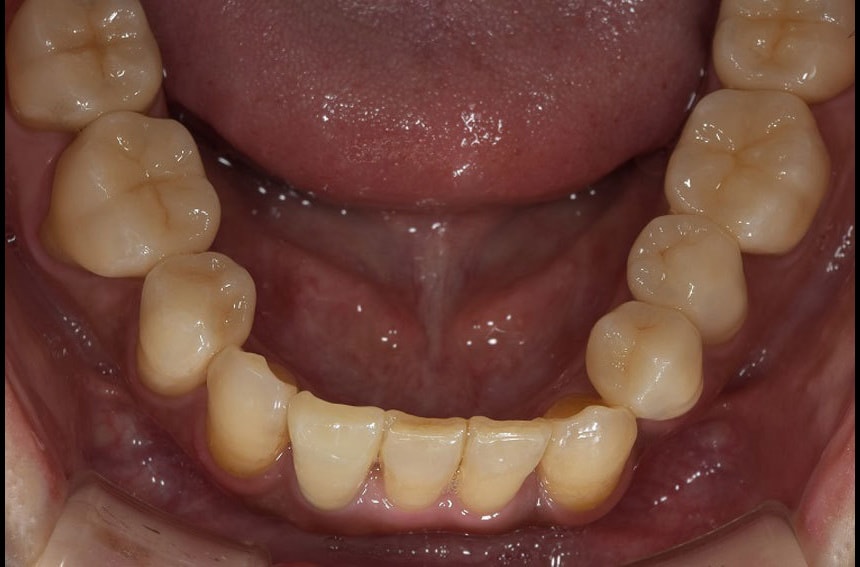

前歯の治療前後

上の歯の治療前後

下の歯の治療前後

最小限の矯正治療や過去に治療した銀歯の隙間から虫歯になった歯や神経の再治療を行いました。もう少し修正が必要なのですが、部分矯正も含め長い治療になり、とりあえずはお疲れさまでした。